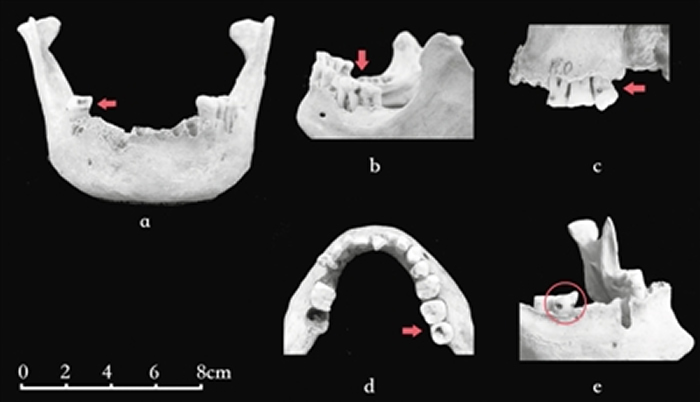

考古发掘中看似微小的龋齿,是如何被考古学家注意到的?牙齿是生物体中最坚硬的组织,因此,它在遗存中最容易被保存下来。一旦被龋蚀,牙齿上会留下明显的痕迹。

现代流行病学常用患龋率(在一定时间内特定人群中患龋人数占总人口基数的百分比)来对现代人龋病情况进行统计。而由于发掘出土的人骨标本的颌骨常常破损,特别是墓葬中散落的牙齿有时很难准确复位到齿槽内,因此研究人员通常根据龋齿数占观察总齿数的百分比来了解古人群龋病情况。